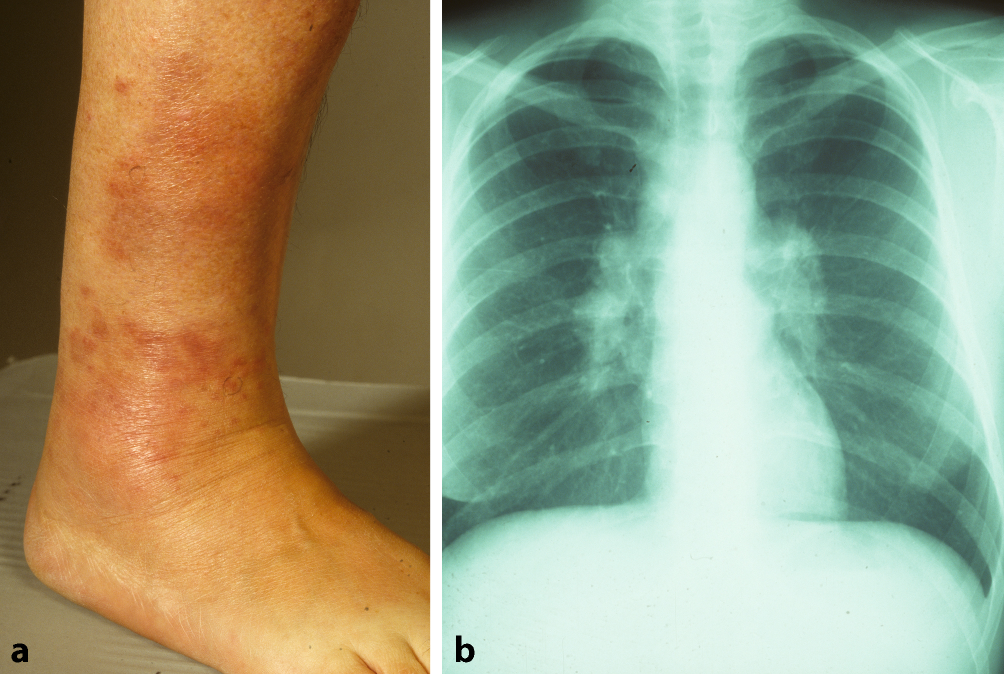

Abb. 3

Löfgren-Syndrom bei einer 63-jährigen Patientin. a Rötliche bis livide Makulae im Bereich des rechten Sprunggelenks (Erythema contusiformis). b Röntgenaufnahme des Thorax mit bihilärer Lymphadenopathie

Bei der Sarkoidose handelt es sich um die häufigste granulomatöse Erkrankung in Nordeuropa. Diese Autoimmun- und Multisystemerkrankung ist der zweithäufigste bekannte Auslöser eines EN weltweit [9]. Etwa ein Viertel aller Sarkoidosepatienten weisen eine Hautbeteiligung auf [1]. Insbesondere ist hier das Löfgren-Syndrom zu nennen, eine Form der akuten Sarkoidose. Klassischerweise wird dies durch die Trias aus Erythema nodosum, Arthritis der Sprunggelenke und bihiläre Lymphadenopathie, häufig in Kombination mit Fieber, definiert. Allerdings gilt es zu beachten, dass bei manchen Patienten weder arthrosonographisch noch magnetresonanztomographisch Zeichen einer Arthritis bzw. ein Gelenkerguss festzustellen sind [10]. Tatsächlich handelt es sich jedoch häufig um eine diffuse, perimalleoläre und nicht zwingend nodöse periartikuläre Pannikulitis, ein sog. kontusiformes („prellungsähnliches“) EN [11]. Diese Veränderungen gehen meist dem typischen Erscheinungsbild des EN im Rahmen eines Löfgren-Syndroms voraus (Abb. 3a). Des Weiteren ist nicht in allen Fällen eine typische bihiläre Lymphadenopathie in der Röntgenübersichtsaufnahme (Abb. 3b) detektierbar, sondern möglicherweise sind entsprechende Befunde hilär und mediastinal erst im Computertomogramm zu sehen.

Das Löfgren-Syndrom ist eine spontan remittierende Erkrankung ohne Tendenz zur Rekurrenz. Wichtig hierbei zu beachten ist jedoch, dass die Kombination aus EN und vergrößerten hilären Lymphknoten auch im Rahmen eines Lymphoms oder einer Tuberkulose auftreten kann [4].

Das erste Symptom eines Löfgren-Syndroms ist häufig ein perimalleoläres, kontusiformes EN.